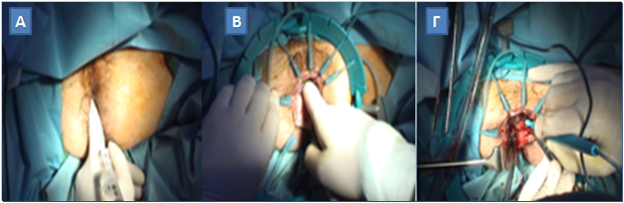

Το πρώτο βήμα του περινεϊκού χρόνου της επέμβασης συνίσταται στην επίτευξη καλής έκθεσης του πρωκτικού καναλιού με την τοποθέτηση ενός ειδικού αυτοσυγκρατούμενου διαστολέα (Lone Star Retractor; Lone Star Medical Products Inc., Houston, TX, USA), ο οποίος διαθέτει λεπτά άγκιστρα για την αποφυγή τραυματισμού του σφιγκτήρα, αλλά και την επαρκή εξάλειψη της σχισμοειδούς διαμόρφωσης του πρωκτικού ανοίγματος, προκειμένου τη διευκόλυνση των διαπρωκτικών χειρισμών επί του ορθικού βλεννογόνου. Στο μεσοσφιγκτηριακό χώρο ανάμεσα στον έσω και στον έσω σφιγκτήρα εγχέεται διάλυμα 1 mg επινεφρίνης σε 20 ml φυσιολογικού ορού, προκειμένου τη διευκόλυνση της μεσοσφιγκτηριακής παρασκευής, αλλά και την ελαχιστοποίηση της αιμορραγίας με τη βοήθεια της τοπικά αγγειοσυσπαστικής δράσης της επινεφρίνης. Ο ορθοπρωκτικός βλεννογόνος με τον υποκείμενο έσω σφιγκτήρα διατέμνονται περιμετρικά σε απόσταση τουλάχιστον 1 εκατοστού από το περιφερικό άκρο του όγκου. Το ορθοπρωκτικό κολόβωμα που δημιουργείται συγκλείεται με ράμμα περίπαρσης για την παρεμπόδιση διασποράς καρκινικών κυττάρων κατά την επακολουθούσα περινεϊκή παρασκευή.

Περινεϊκοί χρόνοι της μεσοσφιγκτηριακής εκτομής: Α. Διήθηση με επινεφρίνη. Β. Τοποθέτηση του ειδικού άγκιστρου Lone Star. Γ. Μεσοσφιγκτηριακή παρασκευή

(Από το προσωπικό αρχείο του Γ. Θεοδωρόπουλου)